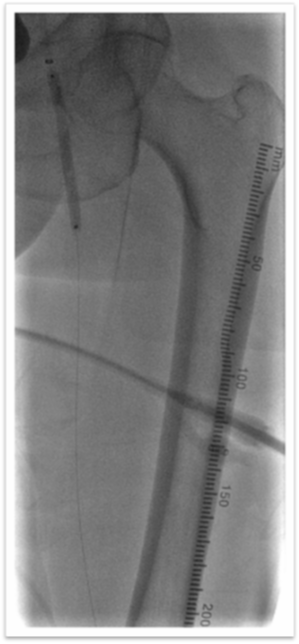

图为:导丝通过病变 置入保护伞 使用Turbohawk定向旋切

图为:股总动脉珊瑚礁病变定向旋切结果股浅动脉段尚未完成定向旋切

图为:血管准备:股浅旋切后球囊全程节段逐级式扩张

图为:评估血管准备:闭塞段残余狭窄90% ELUVIA全覆盖该区域病变